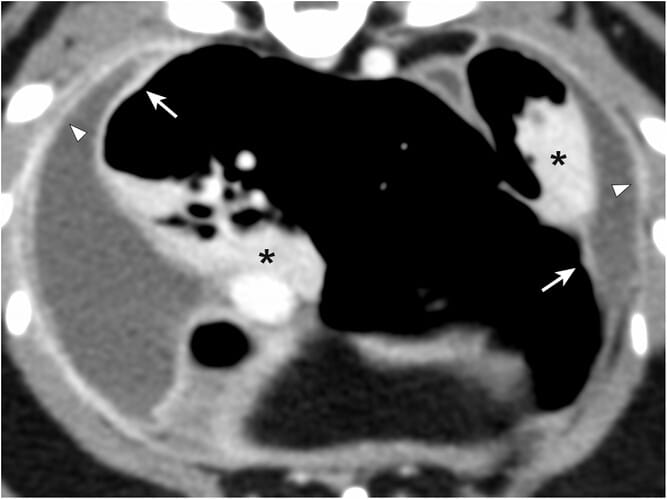

Postcontrast soft tissue algorithm thoracic CT images of a cat (WL 41 WW 400, slice thickness1.25 mm). There is bilateral moderate pleural effusion. The visceral (arrows) and parietal pleura (open arrows) are markedly thickened. In the right and left caudal lung lobe, there are subpleural broad-based masses (asterisks) with the markedly thickened visceral pleural surface. The hilar aspect is irregular and indistinct with incoming vessels and bronchi forming air bronchograms. Both masses are homogeneously strongly enhanced

Results: The authors identified five cases that met the inclusion criteria: four cats and one dog. All cases had pleural effusion, mostly due to idiopathic chylothorax. All cases had subpleural pulmonary masses that were broad-based, homogeneously enhanced, and had indistinct margins at the hilum. The comet tail sign, which is a common feature of rounded atelectasis in humans, was seen in 14 of 26 masses. Other findings included pleural thickening, ground glass opacities, parenchymal bands, lymphadenopathy, and compensatory hyperinflation. Histopathology revealed atelectasis with pleural folding, chronic pleuritis, and mild to moderate pleural fibrosis in all cases.